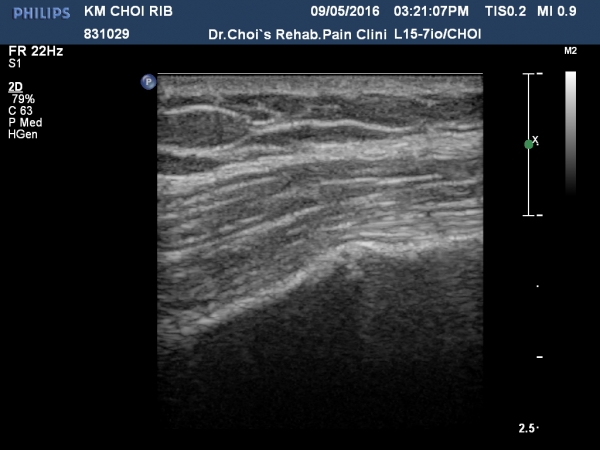

3ÁÖ ÈÄ ÃßÀû°Ë»ç¿¡¼­ °¡°ñ(callus)Çü¼ºÀÌ °üÂûµÈ´Ù(»çÁø 5, 6, 7, 8).